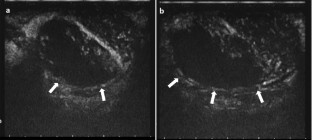

Intratesticular hematoma is one of the most frequent presentations of scrotal trauma. Ultrasound is the first-line imaging modality in the evaluation of scrotal trauma, and its findings are crucial for the choice of treatment. An intratesticular hematoma may represent a diagnostic pitfall for the investigating physician since its appearance may mimic other conditions, such as testicular neoplasms or segmental infarction. Although the gold standard imaging modality for the characterization of a testicular lesion is contrast-enhanced magnetic resonance (MR), MR equipment is not always available in an emergency department. Contrast-enhanced ultrasound (CEUS) may represent a valid and cheaper alternative compared with MR, which may aid the physician in the differential diagnosis. We describe the case of a 19-year-old male with a scrotal trauma following a motorcycle crash. In accordance with the literature, we carried out a contrast-medium whole-body computed tomography for the evaluation of any potential traumatic injury. Because of scrotal swelling and the patient complaining about pain in the right testicle, we performed a scrotal ultrasound, which demonstrated an enlarged right testicle, with an inhomogeneous echostructure due to the presence of a hypoechoic area in the middle and upper portion of the testicle. Color Doppler ultrasound did not show signals of intralesional vascularization. The lesion, although having characteristics compatible with hematoma, must not be diagnosed as testicular neoplasia, segmental infarction, or other mimics. For more information, a CEUS examination was performed. The examination clearly showed the extent of the lesion, the integrity of the testicular capsule, and the absence of internal vascularization; all these findings were regarded as indicators of a testicular hematoma. After the urological examination, the patient was prescribed antibiotic therapy and bed rest. For further confirmation of the CEUS examination, an MR was performed 2 days later, showing a perfect correspondence with the CEUS findings. Our case demonstrates that CEUS is a faster, cheaper, and valid alternative to MR in an emergency setting, as in testicular trauma, in which the hematoma may mimic conditions (neoplasm) that require a different treatment.

Fig. 2